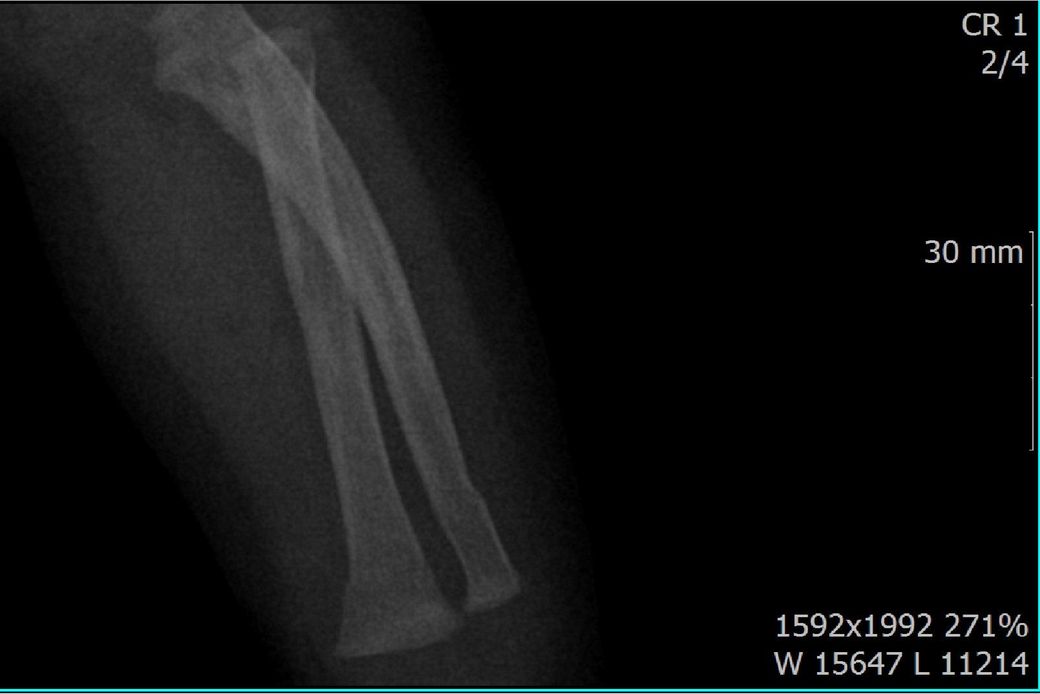

다름이 아니라, 첨부드린 엑스레이(X-ray) 사진처럼 골절 사실을 알게 되고 골절 발생 시점 대략적으로나마 추정시기를 파악하려고 문의 드리게 되었습니다

1) 3월 30일 촬영한 X-ray만으로 정확한 골절 시기를 100% 특정하는 데에는 한계가 있다는 점 충분히 인지하고 있기에 촬영날짜 기준으로 대략적으로 어느정도 시점에서 발생되었을 것으로 추측(ex 당일, 7~10일전, 7~14일 전, 10일 ~ 20일전, 14일 ~ 30일전 등등등)되는지 이해하고 싶습니다.

• 2번 째 사진

골절의 상태를 보고 골절선이 선명하고 부위에 가골이 형성되지않았다면 보통 일주일 이내로 봅니다.

골절선이 보이지만 주변 부위에 가골이 조금씩 있다면 2주 이내.

골절선이 잘안보이고 가골이 보인다면 한달 이내로 판단 할 수 있습니다.